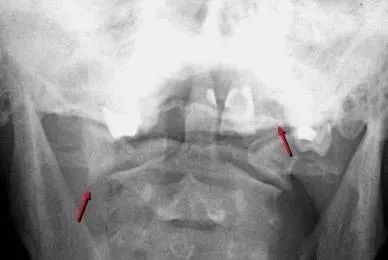

三、Jefferson骨折

为C1爆裂性骨折,多由压缩性外力造成,表现为C1双侧前后弓断裂,张口位显示:寰椎双侧分离移位,不伴有神经损伤。